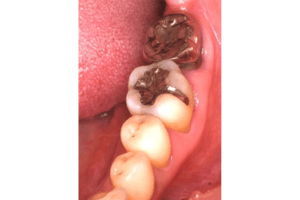

銀歯の中身の写真

麻布十番の歯医者さんで銀歯を外す前の症例写真

麻布十番の歯医者さんで銀歯を外す後の症例写真

こちらは銀歯を外す前と後の写真の比較になります。黒い部分が虫歯になっています。銀歯をつけているとなかなかレントゲンにも虫歯として映ってこないことが多いので、発見が遅れてしまうことがあります。